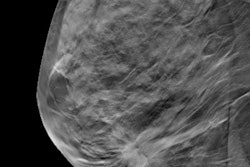

They are protesting an announcement made by BreastScreen NSW on 16 August to suspend all routine mammograms in the state to allow healthcare staff to assist in managing the COVID-19 pandemic. The suspension began on 18 August.